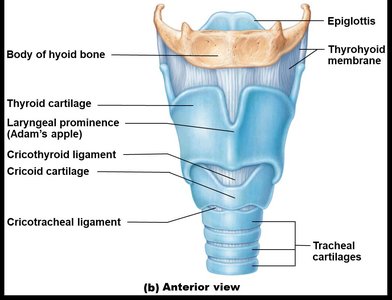

The Larynx

The larynx connects the pharynx to the trachea and is responsible for voice production, maintaining an open airway, and routing air and food using the epiglottis.

Cartilages: Includes thyroid, cricoid, arytenoid, and epiglottis.

Vocal Folds: True and false vocal cords for sound production and airway protection.